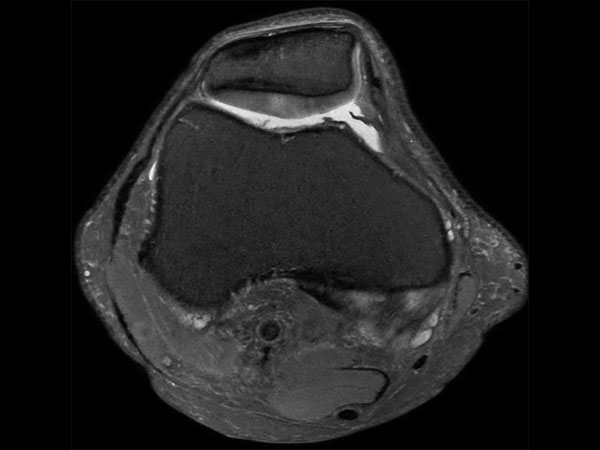

Middle aged board surfer presents with chronic knee pain. X-Ray shows no abnormalities. Follow-up MR examination requested.